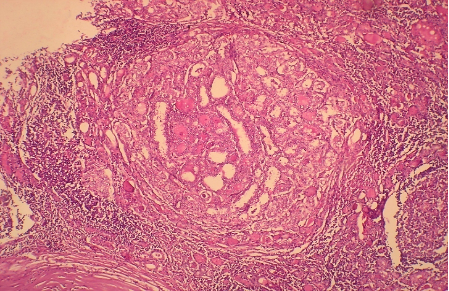

Ultrasonically guided fine needle aspiration cytology of a mass in front of the neck of a 40 year old female. Patient complained of severe back ache and had osteoporosis. Fig 1 and Fig 2 : are shown. Make your diagnosis.

Fig 1

Fig 2

Ans to previous (March 2025):

Excision of the specimen showed a cystic neoplasm (Figs A and B)

Diagnosis: Parathyroid adenoma .